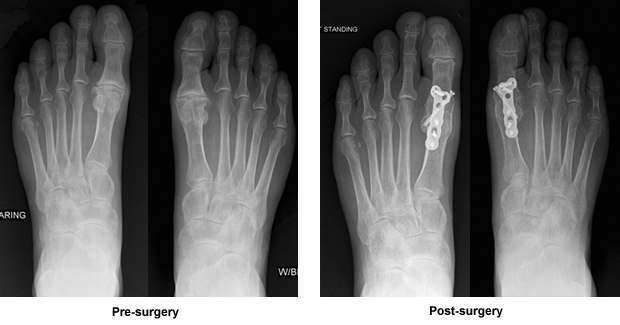

Dr. Leavitt told me I did not have bunions. This was a different problem. My joints were so deteriorated that bone was rubbing on bone. In considering a course of action, he felt bone fusion was a better option than joint replacement. Considering my lifestyle, he determined that joint replacement might need to be repeated eventually and, although I would no longer be able to flex my feet, the problem would be corrected. (I hadn't been able to do that for a long time anyhow and I had already learned how to walk without flexing.) He explained the surgery, long recovery and what I would need to do to insure his work was successful. I went home to think about it. After much thought, I put together a list of questions and e-mailed them to Dr. Leavitt. He called that same day to arrange a time so we could discuss my concerns. Being self-employed, I had many concerns regarding the recovery process. Dr. Leavitt put my mind at ease and answered all my questions. After making some changes in my office and home, I felt ready to have my left foot operated on first.

I had full confidence in Dr. Leavitt and made sure to do everything that he told me to do. That was over a year ago. I heard Dr. Leavitt's voice many times to "protect his work", which I did. I took two weeks off to rest and keep my foot elevated and then eased back into my work schedule. It wasn't easy. I had my right foot operated 10 weeks ago and am doing great!